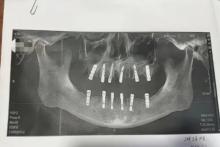

مسئولان چینی در حال بررسی مرگ مرد مسنی هستند که ۱۳ روز بعد از اینکه در یک جلسه درمانی ۲۳ دندان کشید و ۱۲ دندان کاشت فوت کرد.

به گزارش سیتنا، خانم شو (shu)، ساکن شهر یونگ‌کانگ از استان ژجیانگ چین، پس از مرگ پدرش در اثر سکته قلبی، از کلینیک دندانپزشکی محل‌شان شکایت کرد. این زن شواهدی مبنی بر اینکه در یک روز ۲۳ دندان پدرش کشیده و ۱۲ دندان برای او کاشته شده بود به دادگاه ارائه داد و مدعی بود که عوارض درمان دندان‌های پدرش در این کلینیک، ۱۳ روز بعد موجب مرگ ناگهانی او شده است. خانم شو می‌گوید، پدرش تمام ۱۳ روز پیش از مرگش دردهای طاقت‌فرسا داشته است.

بنابر بررسی‌ها، پدر خانم شو،‌ با رضایت کتبی خود اجازه داد تا این درمان سنگین در یک روز انجام شود و یکی از دندانپزشک‌ها که در درمان ریشه دندان، کشیدن دندان عقل نهفته و پروتز کامل تخصص کافی داشت تمام کارهای درمانی دندان پدر خانم شو را انجام داده بود.